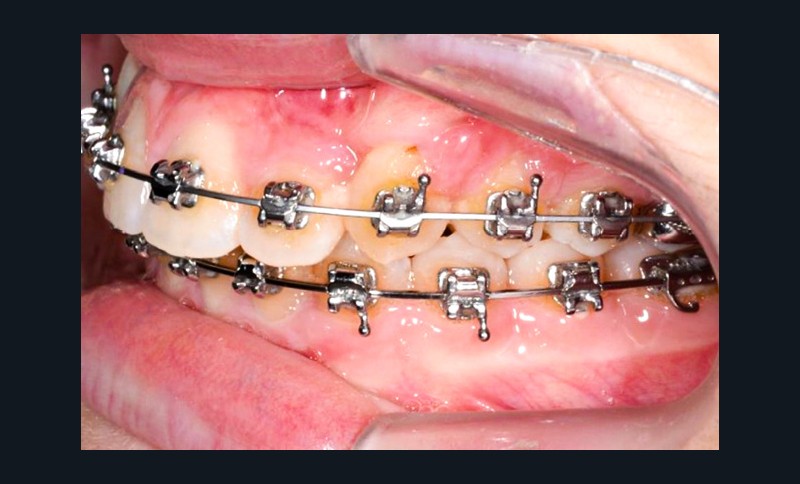

Une fois que la partie en alliage à mémoire de forme de l’arc transpalatin a retrouvé sa forme initiale, l’arc est désinséré. Les U latéraux et les lames d’insertions en acier sont réglés dans les trois sens de l’espace à l’aide d’une pince 139 pour corriger l’inclinaison mésio-distale, le torque et augmenter la dérotation de 16 et 26 pour assurer une traction supplémentaire des canines incluses en direction vestibulaire. Les bras d’expansion des secteurs latéraux de l’arc transpalatin sont également sectionnés. Les bras vestibulaires en TMA sont activés dans le sens vertical pour une traction des canines vers le plan occlusal.